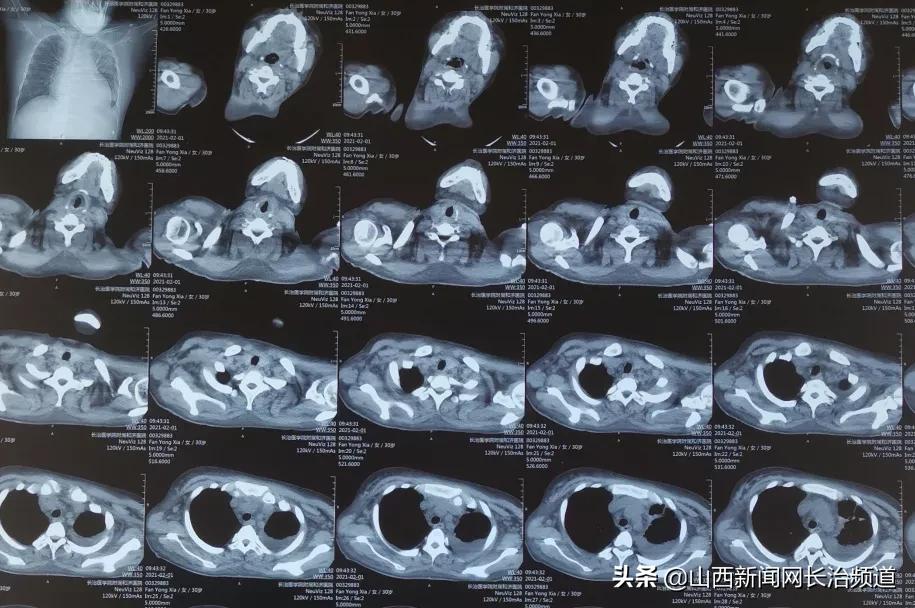

枕顶叶脑出血吸收期

痰栓解除